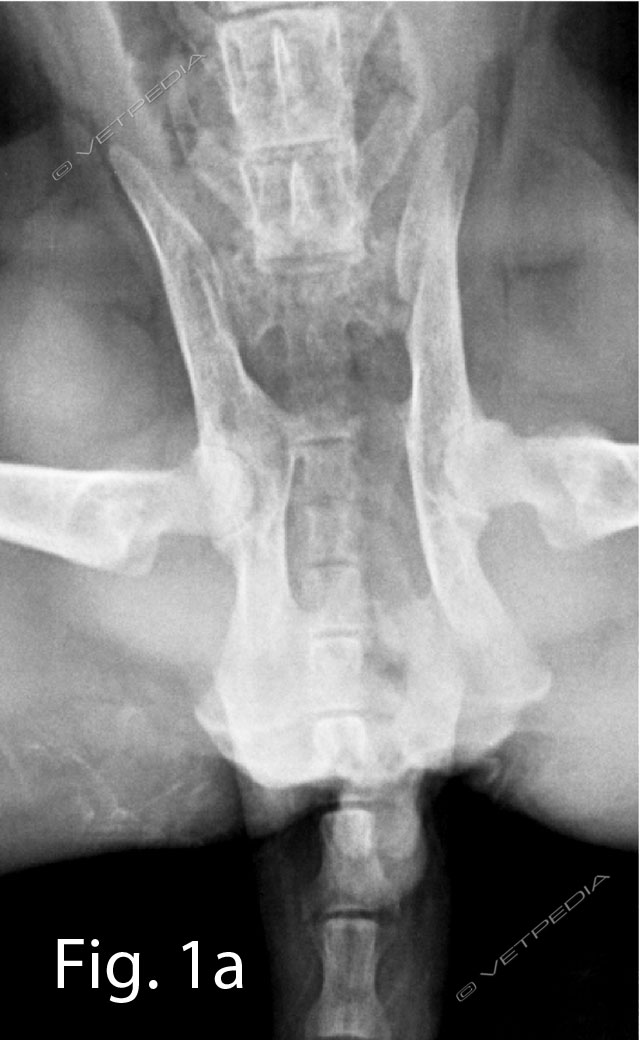

Studi hanno dimostrato che l’eccesso di energia può portare ad una crescita più rapida delle ossa lunghe e un’accelerazione del peso corporeo, che sovraccarica il sistema scheletrico. Un’alimentazione ad libitum può determinare l’insorgenzadelle seguenti patologie ortopediche: osteocondrosi, sindrome del radio curvo, alterazioni della conformazione dell’anca e sindrome di wobbler (Hedhamman et al. 1974) (Figg. 1a e 1b). Viceversa una carenza di energia può portare ad un rallentamento della crescita, ma con la ripresa di una corretta alimentazione il cane cresce più velocemente e più a lungo.